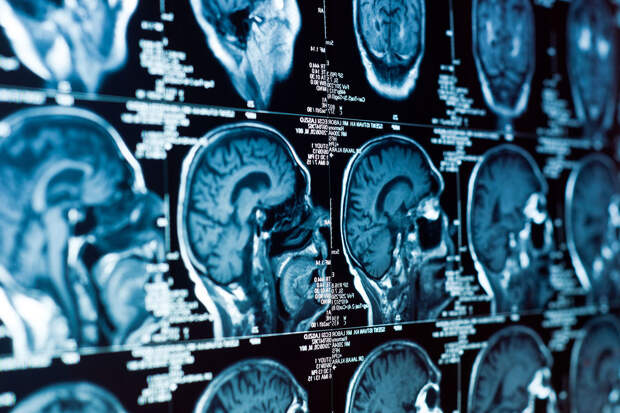

В испытаниях задействовали 18 пациентов с рецидивирующей глиобластомой (опухолью мозга), средняя выживаемость при которой обычно не превышает 6-10 месяцев.